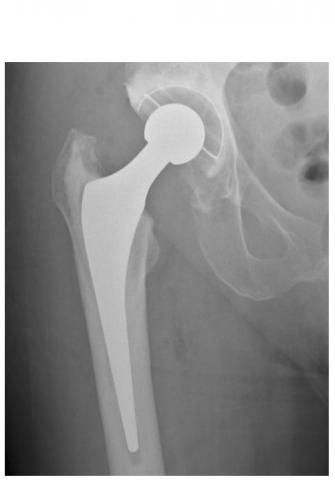

ARTHROPLASTIE de la HANCHE et du GENOU : Un taux de réussite élevé, un résultat durable

Cette intervention désormais classique permettant de rétablir la forme et la mobilité d'une articulation abîmée ou bloquée, que ce soit l’articulation de la hanche ou du genou, atteint aujourd’hui un taux de réussite élevé, conclut cet examen et cette méta-analyse de la littérature. L’équipe de l’Université de Bristol, après avoir examiné des milliers d'études de cas remontant à 25 ans dans 6 pays, estime pour la première fois la durée probable de ces arthroplasties : 80% des arthroplasties du genou et 60% des arthroplasties de la hanche sont toujours en place après 25 ans. Des données très rassurantes, présentées dans le Lancet.

Des variations considérables en fonction des types d’arthroplasties : un remplacement de la hanche comprend principalement 2 composants (col, cavité) mais reste variable dans la manière dont ces pièces sont fixées à l'os, ainsi que dans les matériaux utilisés pour consolider la surface d'appui. Idem pour l’arthroplastie du genou, l’arthroplastie totale va remplacer toute la surface articulaire du patient, tandis qu'une prothèse de genou unicondylienne ne remplace que la partie endommagée du genou. Bref, les variations sont considérables en matière d’arthroplasties de la hanche et du genou, cependant ces facteurs ont bien été pris en compte dans l’analyse.